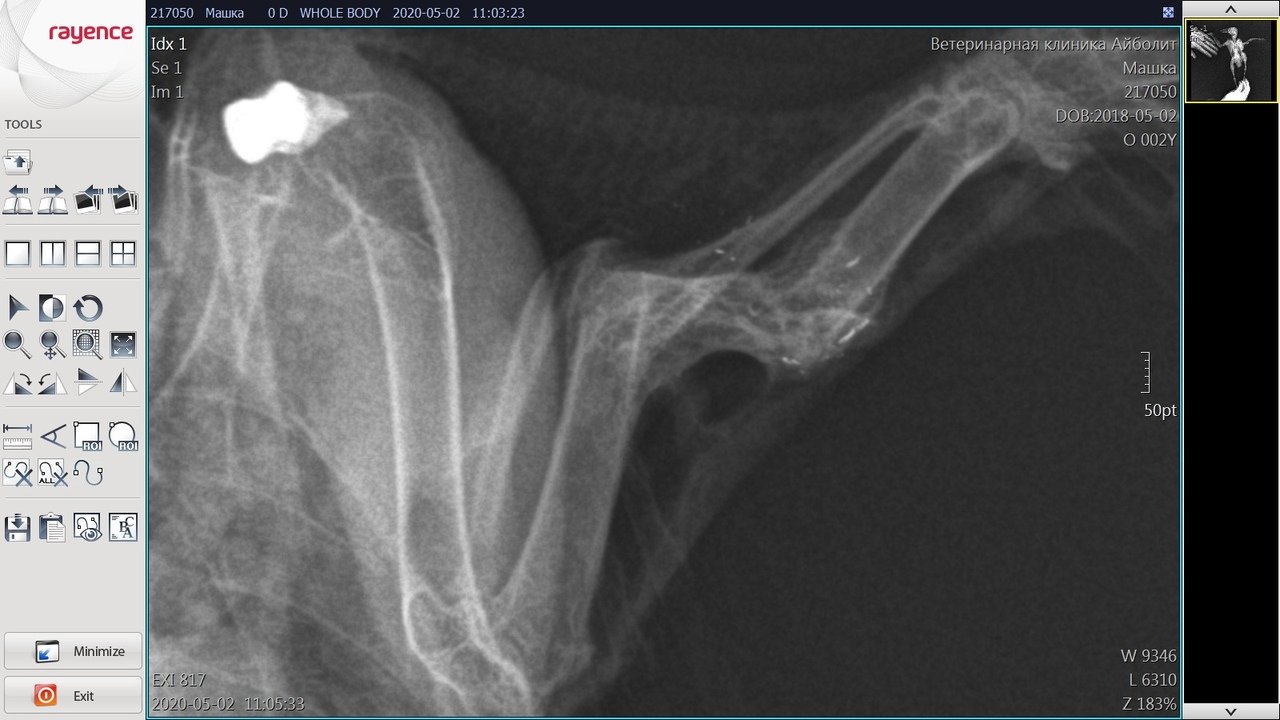

Arizzod Опубликовано 2 июля, 2020 #1 Опубликовано 2 июля, 2020 Птица - ворона; Взрослая, пол не определяли; Питается стандартной мешанкой для врановых, творог, перепелиные яйца, фрукты и овощи; Содержится на лоджии; Мы подобрали ворону, ещё в марте, на крыле не хватало перьев. Подумали, что может потеряла в драке, отрастит и выпустим, но при ближайшем рассмотрении оказалось, что крыло сломано. Птица активная, несмотря на травму весьма бодро перепархивает.За проведённое у нас время с крылом стало хуже. Место перелома сильно её беспокоит, птица постоянно его расклёвывает. Все пеньки новых перьев выдирает, не так давно стала расклёвывать в кровь, сейчас на крыле почти нет перьев, и есть рана. Пробовали заматывать - или слабо и снимает, или сильно, тогда отекает крыло.Были у ветеринара, но там где были нам помочь не смогли, только сделали рентген на котором видно раздробление лучевых костей и пулю от пневмата в плече. расклёвывает место перелома, сама пуля похоже не беспокоит.Очень хочется птицу если уж не вылечить, то облегчить жизнь.